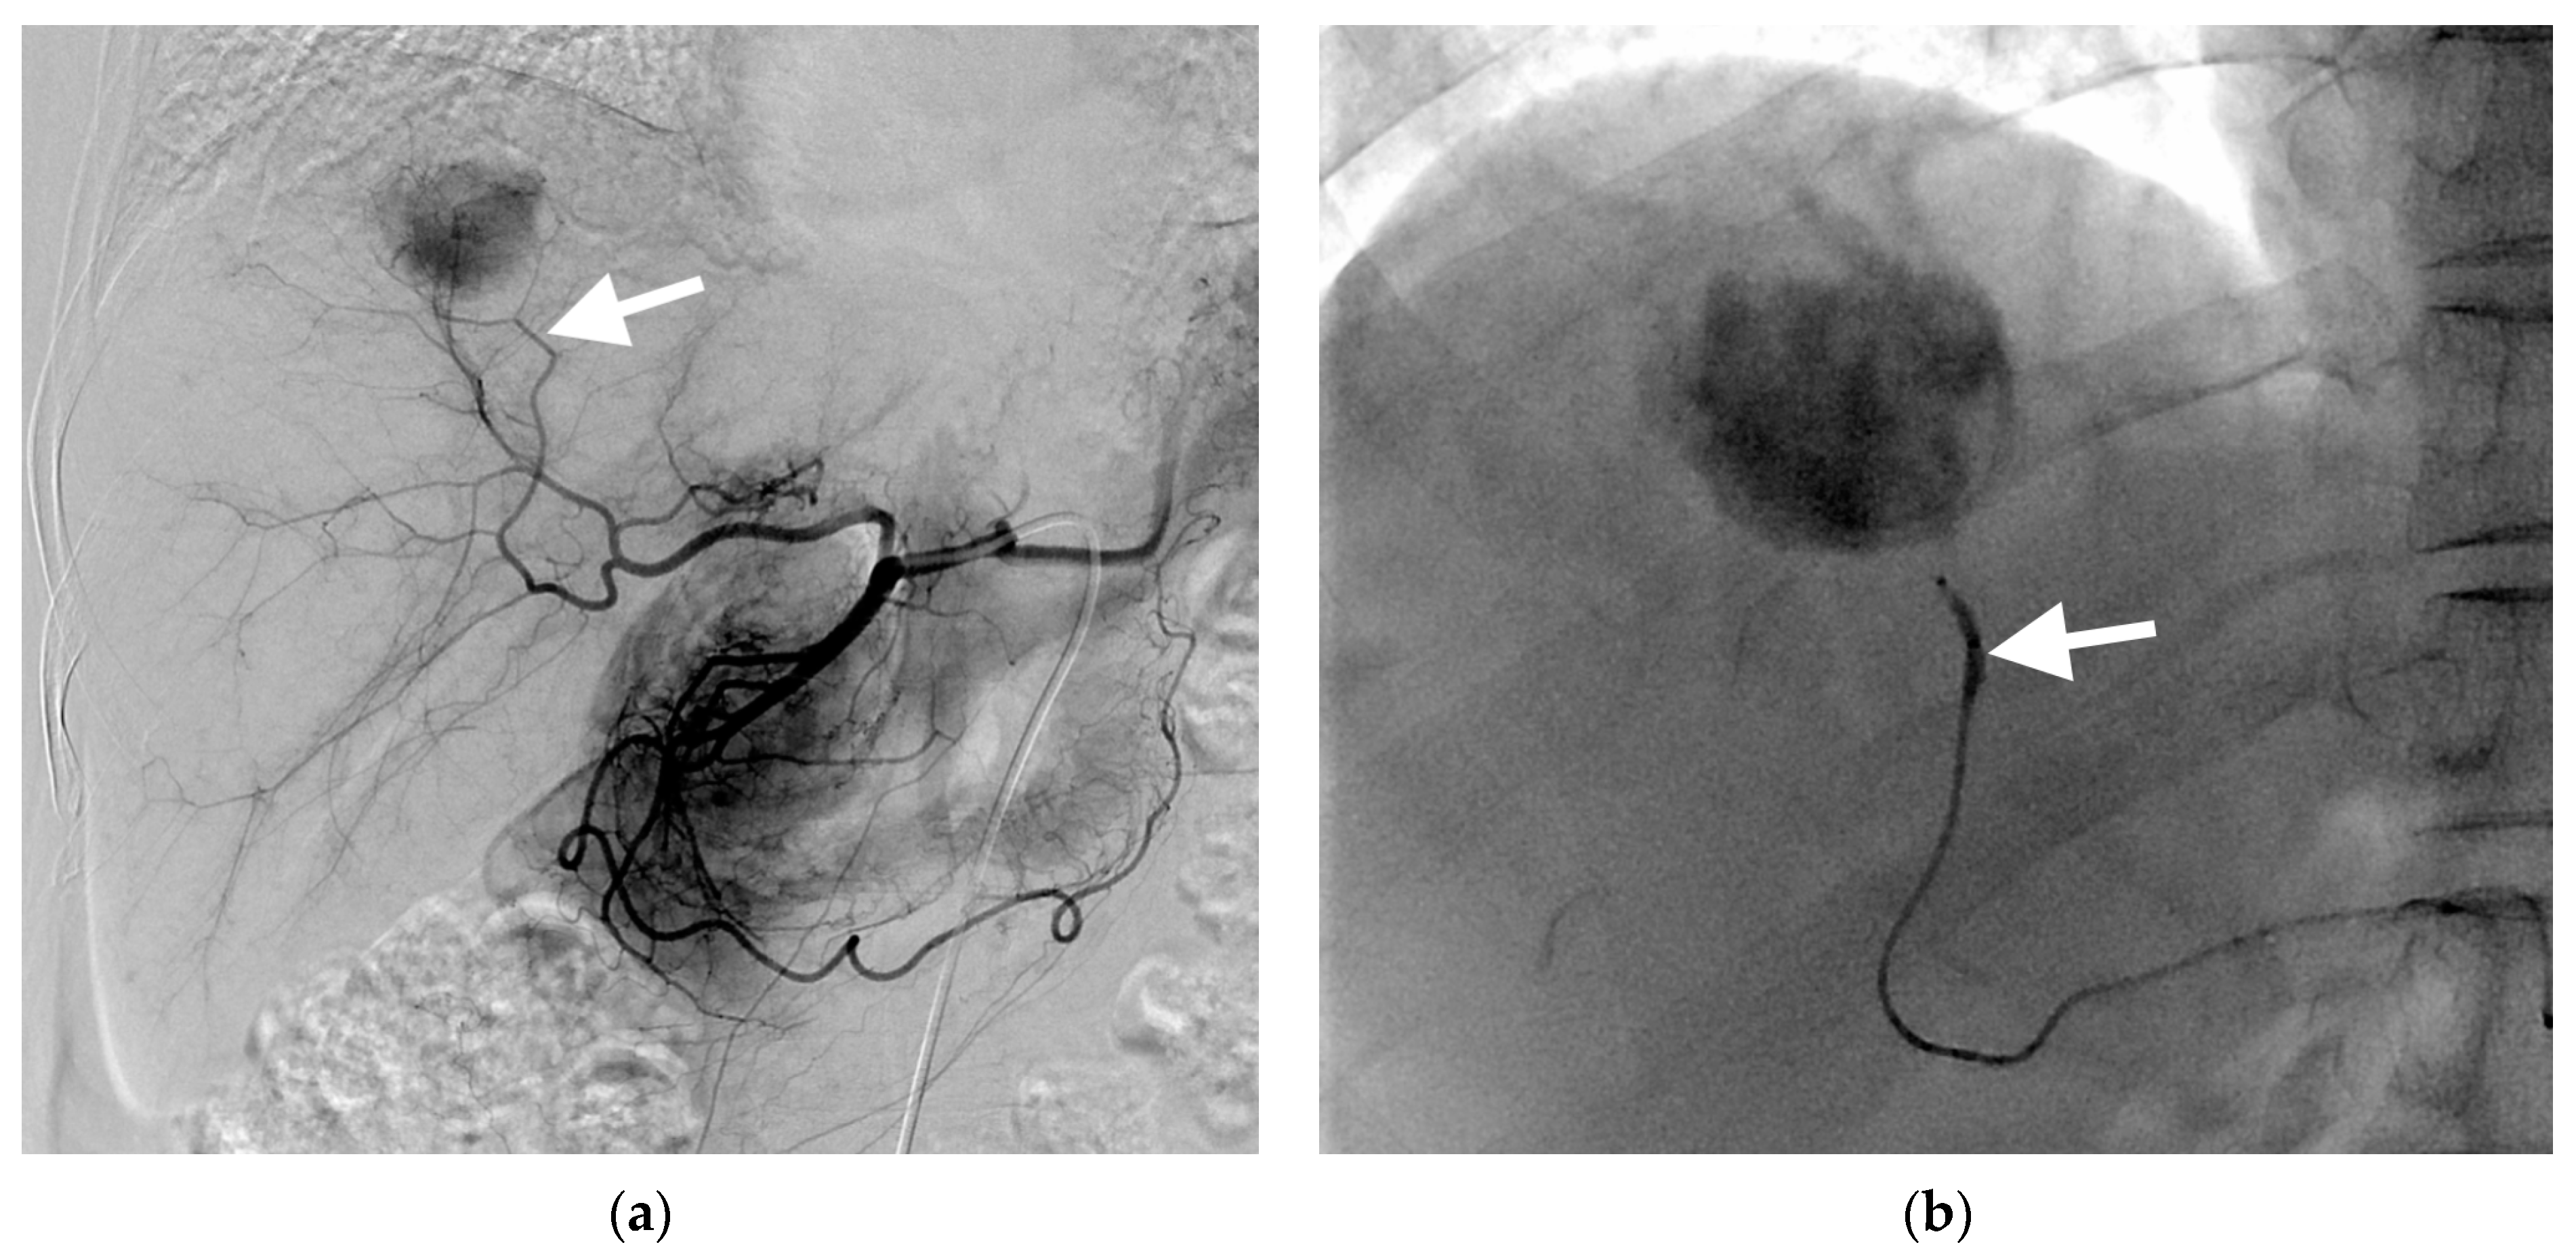

3.1. B-TACE Procedure and Complications

3.2. Follow-Up

3.3. Local Recurrence